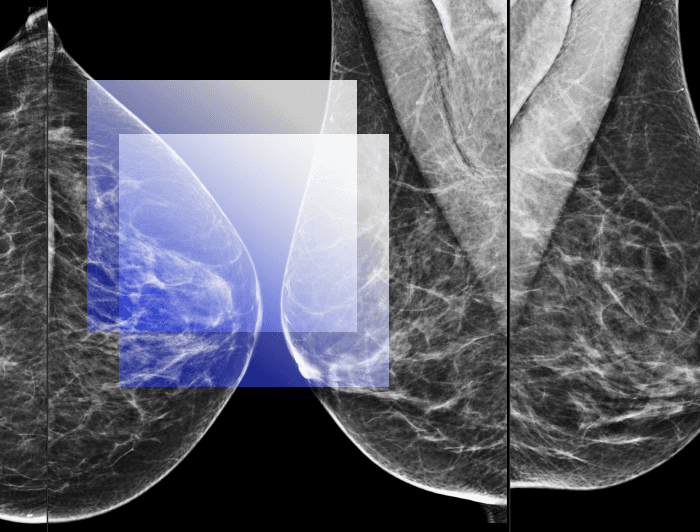

Даний майстер клас надасть вам комплексне розуміння фундаментальних аспектів у маморадіології та підготує вас до ефективної клінічної практики.

Майстер клас підійде радіологам, що бажають поглибити свої знання у візуалізації грудних залоз та початківцям маморадіологам, що прагнуть отримати практичні навички та більшу впевненість в описі мамографічних знімків.